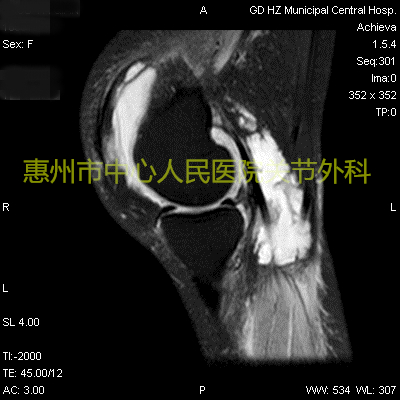

如果配合上抽血,出现血常规白细胞升高,红细胞沉降率、降钙素原、C反应蛋白等感染指标升高,可以更为准确的判断全身感染的程度。有时候医生会建议加做关节磁共振检查,磁共振可以清晰显示关节内脓液的量、软骨/软骨下骨破坏程度及骨髓水肿的程度,脓液由于成分复杂,磁共振常表现为棉絮样混杂信号。

磁共振可以见到关节内大量积液